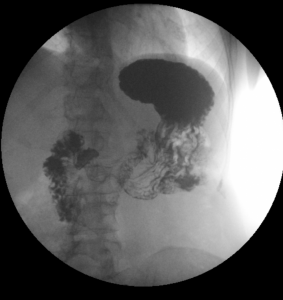

Vyšetření žlučových cest – ERCP (endoskopická retrográdní cholangiopankreatikografie)

ERCP je diagnostická a terapeutická metoda. Kombinuje v sobě endoskopické a radiologické vyšetření. Jejím cílem je zobrazit žlučové cesty a a v případě potřeby také vývody pankreatu. Vyšetření se provádí pod vedením gastroenterologa na radiologickém oddělení.

Tato vyšetřovací metoda je na našem oddělení ze skiaskopických vyšetření nejčastější.

Využíváme C-rameno Multidiagnost Eleva od firmy Philips, digitální zpracování a archivaci nálezů.

V dohledné době očekáváme zakoupení nového skiaskopického kompletu a kompletní přesun vyšetřovny na gastroenterologické oddělení. Provádíme papilotomie, stentáže (plastovými i metalickými stenty), dilatace stenóz žluč. cest, extrakce konkrementů, jejich drcení (mechanickou litotrypsi), vyšetření žlučových i pankreatických cest cytologické a kultivační, nově i endoskopicky, urgentní výkony – zejména při zánětech žluč. cest či slinivky.

Vyšetření se provádí za hospitalizace. Pacient je před vyšetřením informován o jeho průběhu a podepisuje informovaný souhlas. Vyšetření tvá asi 15 až 45 minut, dle rozsahu výkonu. Pacient je v jeho průběhu v poloze na levém boku. Pacientovi se před vyšetřením aplikuje do oblasti kořene jazyka lokální znecitlivění (anestetikum) a do žíly zklidňující léky. V některých případech se preventivně podávají i antibiotika. Lékař následně zavede ústy endoskop (tenkou flexibilní trubici s optikou), pokračuje přes jícen, žaludek až do dvanáctníku, kde nalezne ústí žlučových cest a vývodu pankreatu, tzv. Vaterskou papilu. Poté lékař vysune z endoskopu tenkou sondu, pomocí níž vstříkne kontrastní látku, která zobrazí dle potřeby žlučové cesty nebo vývod slinivky. V této části vyšetření se provede několik rentgenových snímků. Pomocí metody ERCP je možné odstranění konkrementu, rozšíření zúžení žlučových cest či zavádění drénů. Podle potřeby je možné provést biopsii (odběr malého kousku tkáně k histologickému vyšetření).

Toto invazivní vyšetření poskytuje lékařům informaci o stavu žlučových cest a vývodů pankreatu. Na pořízených RTG snímcích mohou být patrná zúžení či úplná neprůchodnost některých jejich částí, které mohou být (kromě jiného) způsobeny i nádorem žlučových cest či pankreatu. V současné době je ERCP často prováděno s terapeutickým cílem.